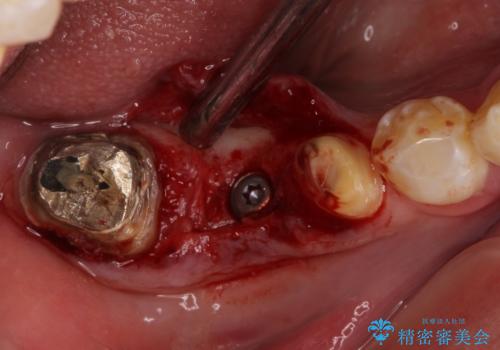

折れてしまった奥歯 インプラントによる補綴治療

- 奥歯に違和感を感じており、抜歯の必要性を感じて来院された患者様です。

診査の結果、5本の奥歯を抜歯してインプラントによる補綴治療が必要と診断されました。

左上の奥歯は2本抜歯が必要であったため、治療期間中は右側に負担がかかり、頻繁に仮歯が壊れてしまいました。